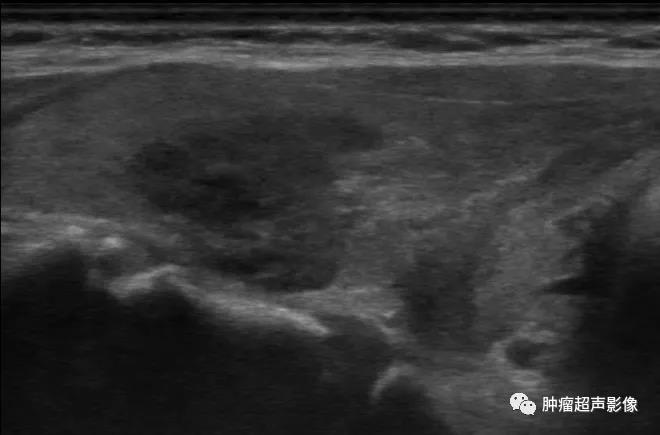

男47,无压痛、无发热,甲状腺左叶低回声,边缘毛刺,无血流,国内某甲状腺顶级医院查左侧甲状腺低回声4类,与甲状腺乳头状癌不好鉴别,病理示肉芽肿性甲状腺炎。